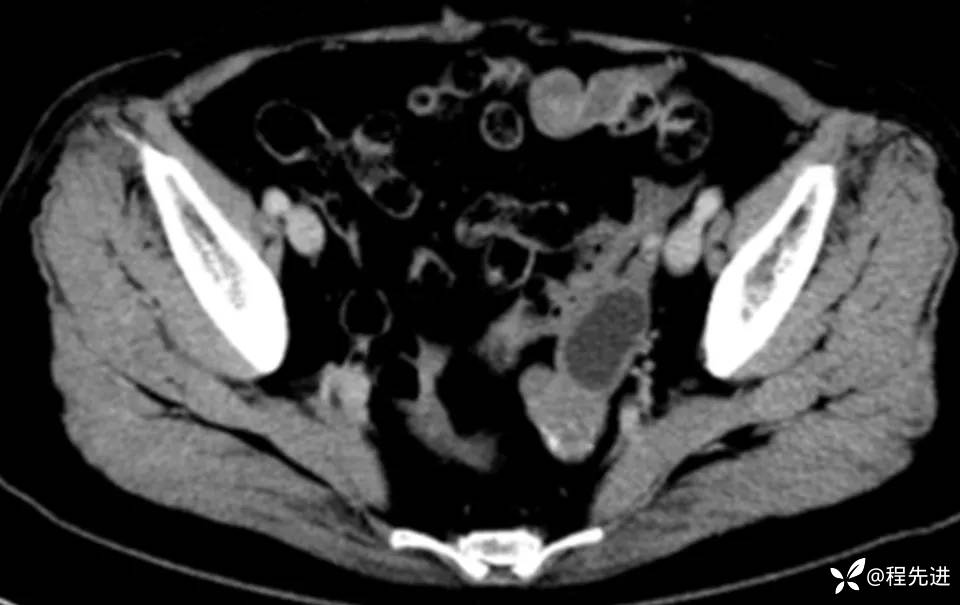

CT平扫+增强:

img